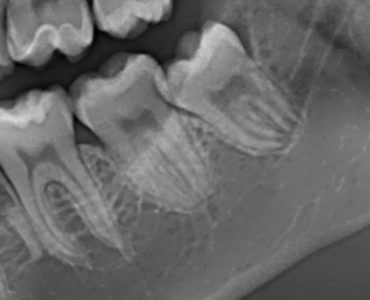

di Luigi Checchi Didascalia foto : L’ortopantomografia (OPT) è l’esame standard per valutare la posizione e l’anatomia del dente del giudizio. In questa immagine si osserva il rapporto di vicinanza tra le radici e il canale mandibolare, punto di partenza per… Leggi

Terzo molare inferiore sinistro a contatto con il canale mandibolare